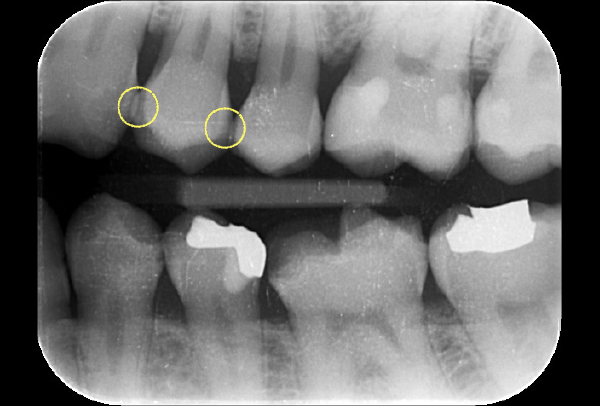

初診時パノラマ

初診時バイトウィングデンタル

レントゲンだとちょっと虫歯が怪しいくらいに写っている。これだけだと確定診断としては、判断材料が少ないと考えられる。

黄色丸の部位が、他の部位と違って白く抜けがあるのがわかります。これがNIRI機能による虫歯の診査です。

この機能のおかげで、歯と歯の間の見つけにくい虫歯がよくわかるようになってきました。